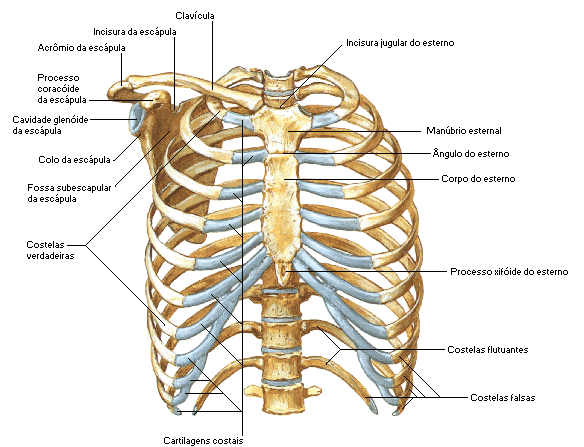

Entorse costal

A entorse costal causa uma dor torácica aguda, normalmente aumentada pela rotação do tronco e respiração, esse tipo de problema é bastante similar ao processo fisiopatológico de uma dor ciática ou de uma nevralgia cervicobraquial. Como ocorre Após um choque direto; um choque anterior produz uma entorse posterior, choque posterior produz entorse condrocostal (anterior). Após […]